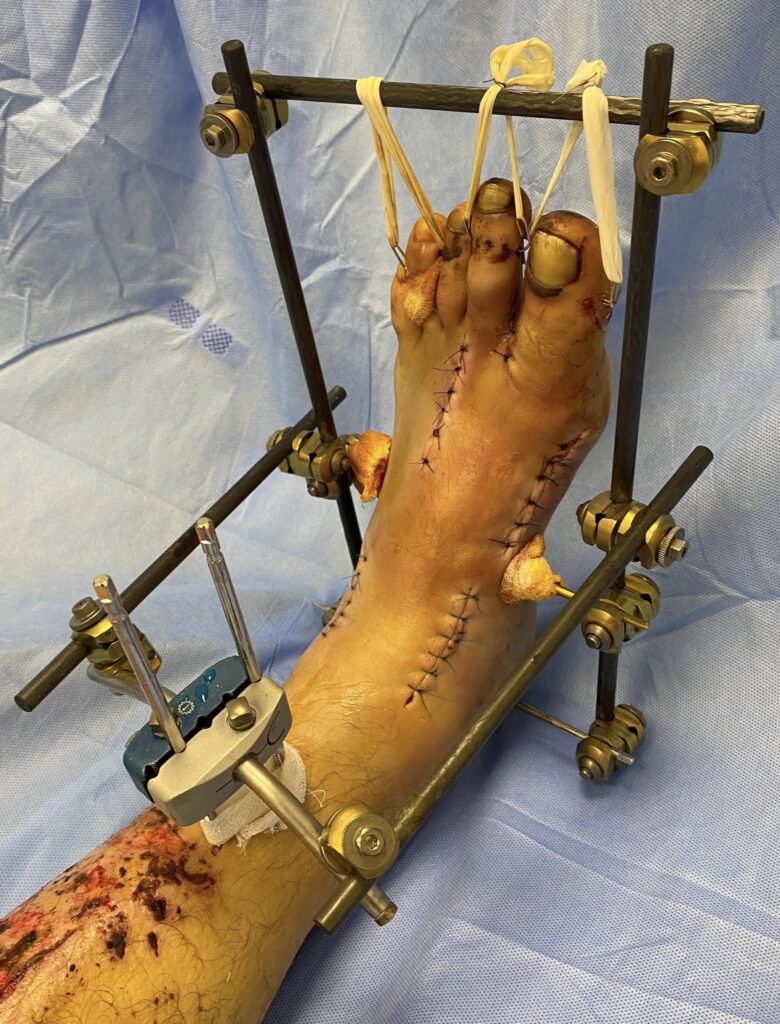

Petro Nikitin:

Наслідки скиду з дрона…

Хірургія стопи сьогодення (…це вам не Халюкси оперувати)

Дякую хірургу Степану Барабашу за чудову роботу